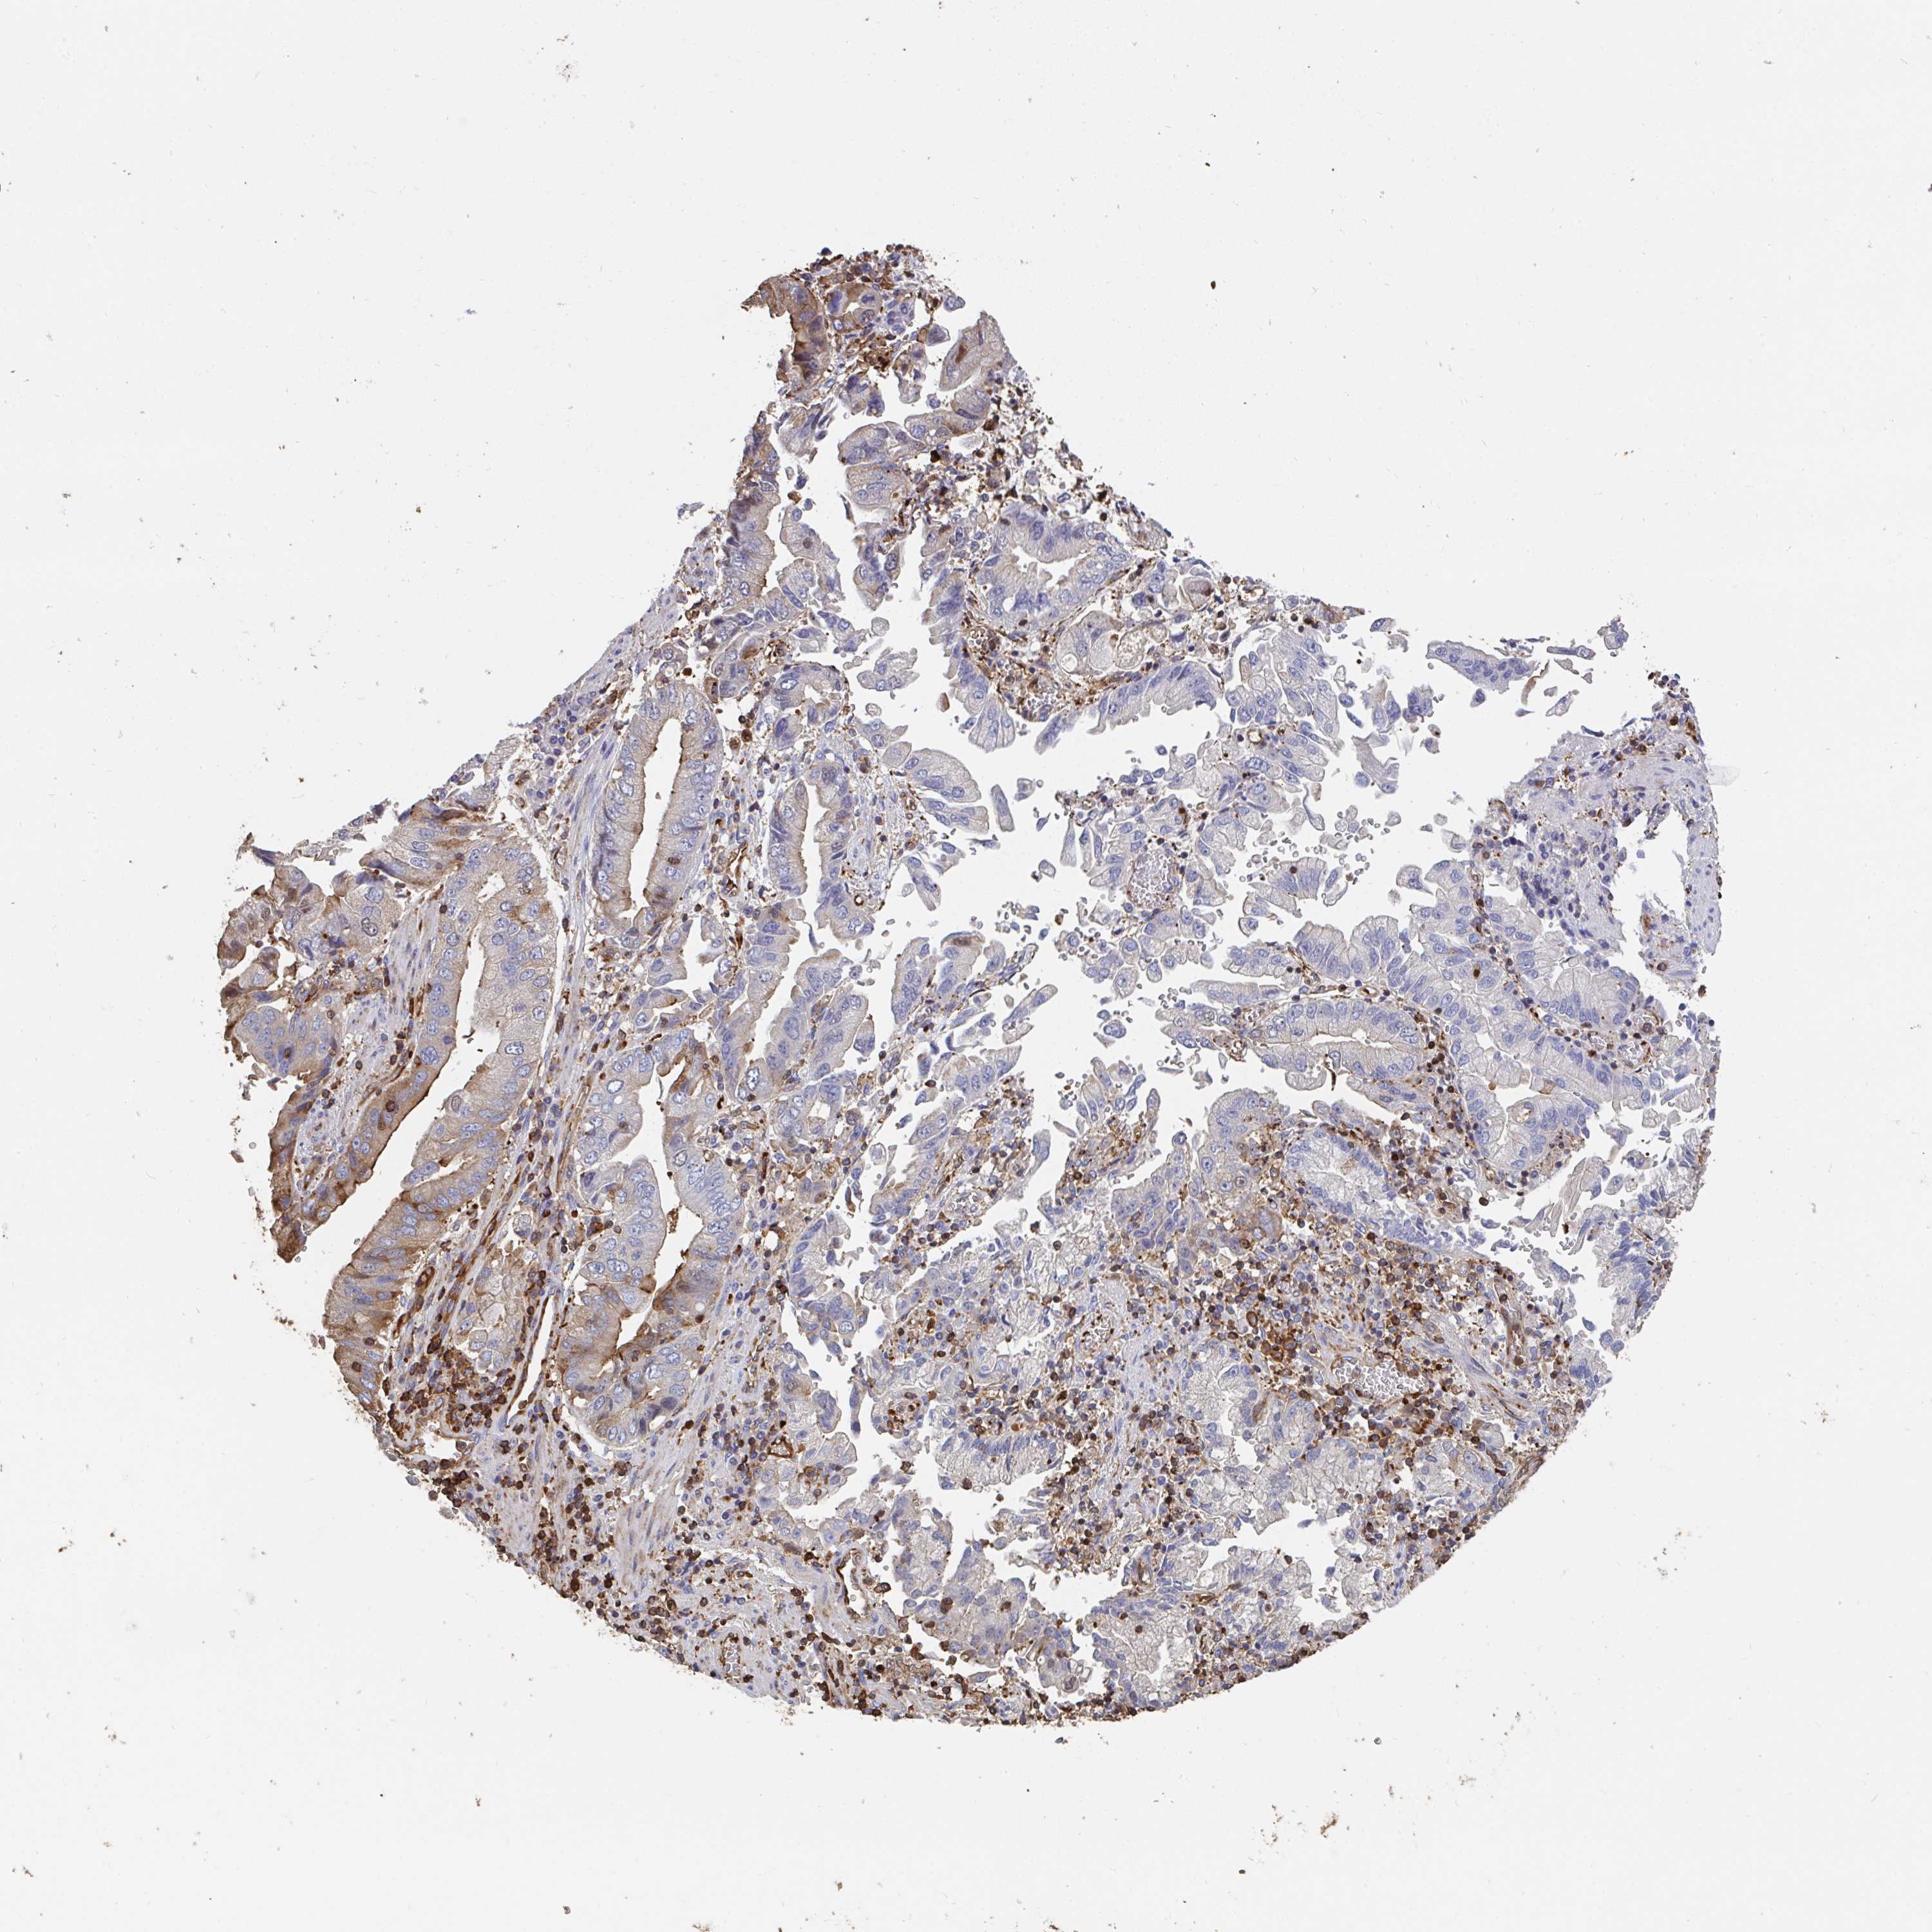

STOMACH CANCER - Protein expressioni

A mouse-over function shows sample information and annotation data. Click on an image to view it in a full screen mode. Samples can be filtered based on level of antibody staining by selecting one or several of the following categories: high, medium, low and not detected. The assay and annotation is described here.

Note that samples used for immunohistochemistry by the Human Protein Atlas do not correspond to samples in the TCGA dataset.

Antibody stainingi

Antibody staining in the annotated cell types in the current human tissue is reported as not detected, low, medium, or high, based on conventional immunohistochemistry profiling in selected tissues. This score is based on the combination of the staining intensity and fraction of stained cells.

Each image is clickable and will lead to virtual microscopy that enables deeper exploration of all samples and also displays staining intensity scores, fraction scores and subcellular localization as well as patient and tissue information for each sample.

Antibody HPA053761

Antibody CAB033687

Antibody CAB037077

Staining

High

Medium

Low

Not detected

Intensity

Strong

Moderate

Weak

Negative

Quantity

>75%

75%-25%

<25%

None

Location

Nuclear

Cytoplasmic/membranous

Cytoplasmic/membranous,nuclear

Adenocarcinoma, NOS